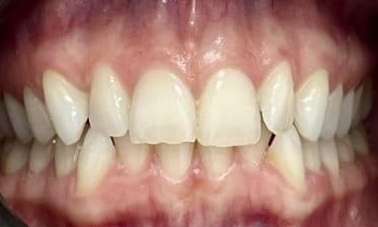

This patient was worried about the incisal edges of her front teeth that had become thin and prone to chipping. This had started in her twenties and unfortunately, now in her thirties, was progressing due to her deep and tight bite and minor crowding.

In her case, Dr Gourlay used 14 series of Invisalign aligners over 14 weeks to align her teeth into a more protected bite pattern. She then used composite bonding to restore the chipped edges. The patient has since moved on to using retainers at night to maintain and protect the position of the teeth.